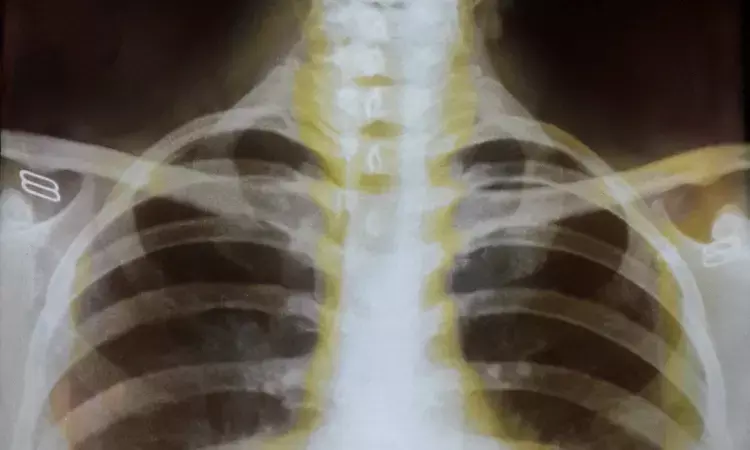

AI detects hidden objects on chest scans better than radiologists, reveals research

Researchers at the University of Southampton have developed an artificial intelligence (AI) tool that can spot hard-to-see objects lodged in patients’ airways better than expert radiologists.

In a study published in npj Digital Medicine, the AI model outperformed radiologists in checking CT scans for objects that don’t show up well on scans.

Foreign body aspiration (FBA) occurs when an object, often food or a small piece of material, becomes lodged in the airways.

When the objects, such as plant material or crayfish shells, are radiolucent (invisible on X-rays and faint even on CT scans), it can be very difficult to detect. This often leads to missed or delayed diagnoses, putting patients at risk of serious complications. Up to 75 per cent of FBA cases in adults involve radiolucent foreign bodies.

To address this challenge, the research team created a deep learning model. It combines a high-precision airway mapping technique (MedpSeg) with a neural network that analyses CT images for hidden signs of foreign bodies.

To put the model to the test, researchers compared its performance to that of three expert radiologists, each with over ten years of clinical experience. The task was to examine 70 CT scans, 14 of which were cases of radiolucent FBA, confirmed by bronchoscopy.

When the radiologists detected a case of radiolucent FBA, they did so with total precision – there were no false positives. In comparison, the AI model did so with 77 per cent precision, detecting some false positives.

However, the radiologists missed a large portion of FBA cases, identifying just 36 per cent of them and highlighting the difficulty humans have in spotting such cases. The AI model, on the other hand, was able to spot 71 per cent of cases, meaning far fewer FBA cases slipped through the net.

In F1 score, which balances precision and recall, the model outperformed the radiologists with a score of 74 per cent vs 53 per cent.